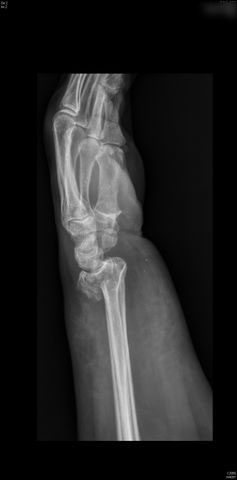

Fractura compleja de húmero.

Fractura de húmero, intensa desviación de fragmentos